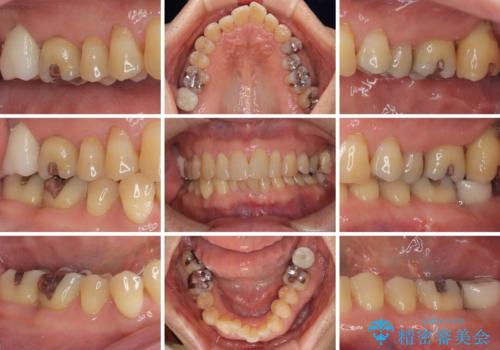

外側に飛び出している歯 部分矯正を用いた奥歯の補綴治療

上顎左右の歯をアンカースクリューを用いた部分矯正により位置を修正し、オールセラミッククラウンにて補綴治療を行うこととしました。

矯正治療に時間はかかりましたが、外側に飛び出した歯が内側に収まったことで、非常に歯が磨きやすくなったとのことでした。